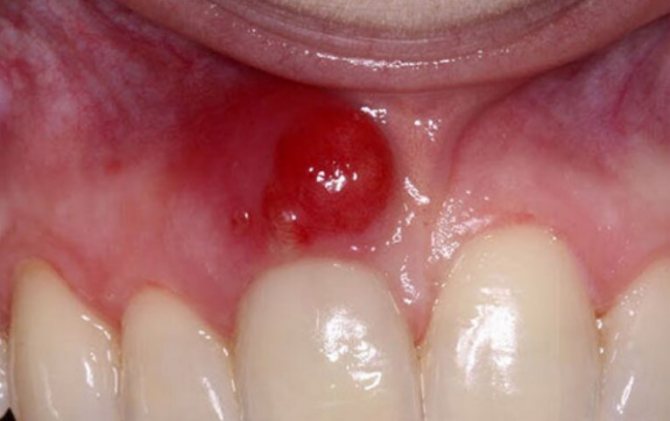

Рак слизистой оболочки десен имеет обычную для раков полости рта папиллярную, бугристую или язвенную форму. Наблюдаются легкая кровоточивость, инфильтрация в глубину, распространение по поверхности с переходом на преддверие рта и щеку и метастазы в железы на шею.

Диагноз на основании изложенных признаков, появляющихся у пожилых людей, не особенно труден, но все же должен быть дополнен биопсией. Разрыхление десен при цинге бывает разлитое, по всему протяжению челюстей, а при раке ограниченное. Эпулиды челюстей характеризуются наличием ножки с подвижной опухолью, истинные саркомы альвеолярных отростков представляют более массивные опухоли, покрытые вначале гладкой слизистой оболочкой. В стадии изъязвления диагностические ошибки возможны, и биопсия имеет решающее значение.